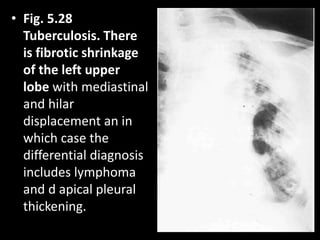

• Fig. 5.28

Tuberculosis. There

is fibrotic shrinkage

of the left upper

lobe with mediastinal

and hilar

displacement an in

which case the

differential diagnosis

includes lymphoma

and d apical pleural

thickening.

• Fig. 5.28 Tuberculosis.There is fibrotic shrinkage of the left upper lobe with mediastinal and hilar displacement an in which case the differential diagnosis includes lymphoma and d apical pleural thickening.